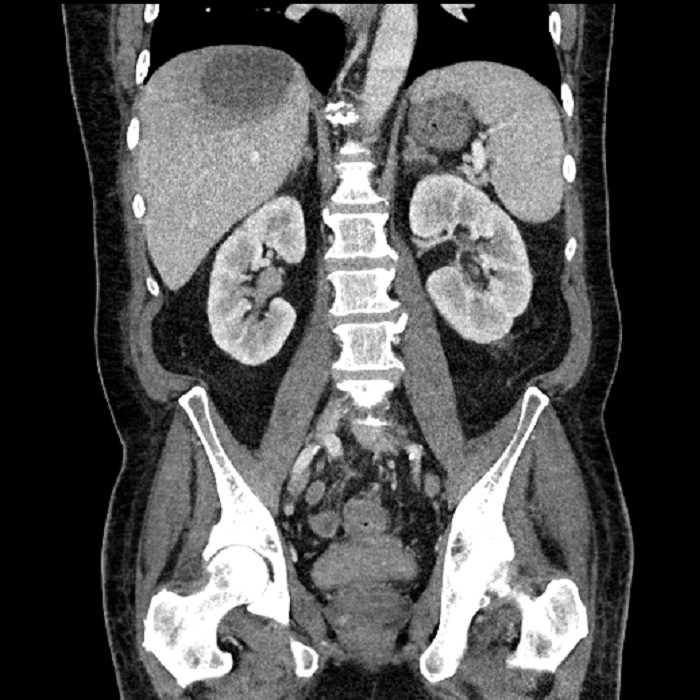

Age: 63

Sex: Male

Indication: Abdominal pain

• Large fluid density structure in hepatic segments 7 and 8 measuring 10 x 7 x 7 cm with internal septation and circumferential ill-defined low density compatible with edema

• Peripherally enhancing subcapsular collections along the anterior margin of the left hepatic lobe measuring 3 x 1 cm and 2 x 1 cm

• Clearly marginated fluid density structure in segment 7 and several other scattered tiny hypodensities, which likely represent cysts

• High grade stenosis of the left common iliac artery, with the left internal and external iliac arteries remaining patent

• Ankylosis of both sacroiliac joints

• Hepatic abscess

Acute sigmoid diverticulitis complicated by a small contained perforation and a large abscess in the right hepatic lobe. Additional small subcapsular abscesses along the anterior margin of the left hepatic lobe.

High grade stenosis of the left common iliac artery. The left external and internal iliac arteries are patent.

Hepatic abscess showing the double target sign with low density internally surrounded by a thin inner enhancing rim (red arrow) and ill-defined outer low density rim (yellow arrow). Blue arrow indicates an internal septation. Red arrows: additional smaller subcapsular abscesses. Red arrow: focal contained perforation associated with diverticulitis.